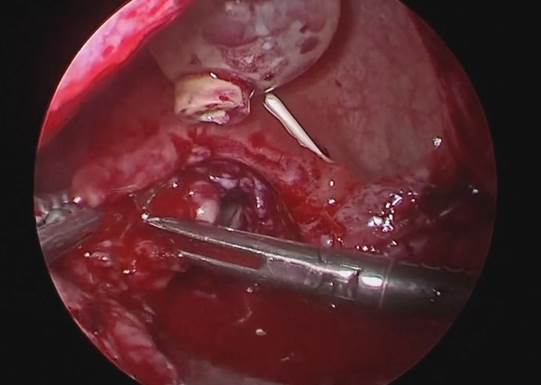

6. Reparación de la fístula. Se diseca la pared posterior de la vejiga de la pared anterior de la vagina con disección roma o cortante. Se procede a realizar fistulectomía circunferencial con corte frío (Fig. 8), se completa disección y separación de pared vaginal de la vesical (Fig. 9).